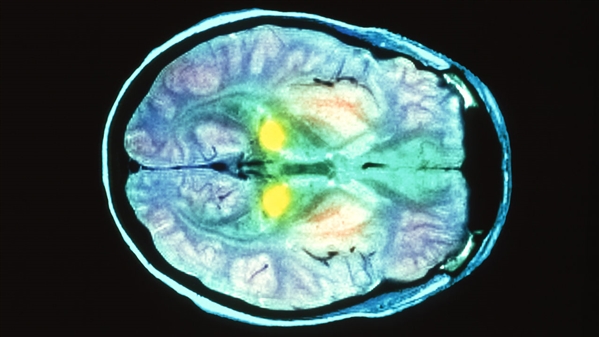

阑尾和扁桃体样本分析显示,英国每2000个人中就有一个朊病毒携带者。没有人知道最终会有多少携带者发展成为vCJD。这一疾病的潜伏期可以长达50年。一旦症状发生,受感染的人会出现幻觉、睡眠紊乱、失语症、肌肉萎缩和进行性痴呆等症状,并会在发病的一年内死亡。已知有四个人通过无症状携带者的输血而感染了vCJD。

由于朊病毒在血液中数量极少,所以筛查很困难。在《科学—转化医学》上描述的新筛查方法都依赖于通过用正常蛋白质培养,声波搅动扩增朊病毒。美国得克萨斯大学神经生物学家Claudio Soto团队和法国蒙彼利埃大学微生物学家Daisy Bougard团队利用该方法,对来自英国和法国的克雅氏病患者的血液样本进行了测试,结果显示这一检测方法具有100%的准确度。

这一方法不仅可以精确诊断出克雅氏病,而且可以在患者发展出症状之前就检测到,这对于欧洲这种有大量无症状携带者的区域而言意义重大。不过,目前的测试方法比较复杂,不适合大规模的血液筛选,但可以用于精确诊断,特别是在无症状携带者或接受了携带者输血的高危人群中。另外,这些研究都没有分析足够的样本,以预测假阳性概率。(张章)http://news.sciencenet.cn/htmlnews/2016/12/364420.shtm